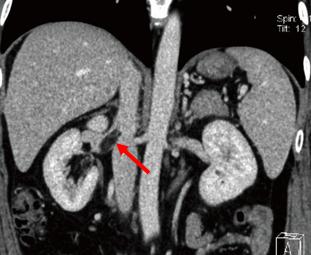

虽然错构瘤为良性肿瘤,但是部分病例有恶性生物学行为,图中箭头所示错构瘤长入下腔静脉,形成腔静脉内瘤栓

总的原则是 一是保命、二是保肾。极少数错构瘤有恶性生物学行为,形成静脉瘤栓或由侵袭行为(见上图),需积极手术治疗。本科室完成了2例错构瘤合并下腔静脉瘤栓的患者,手术方式是 下腔静脉瘤栓取出术+工作台肾错构瘤切除术+自体肾移植术,成功的为患者保住了 肾脏。